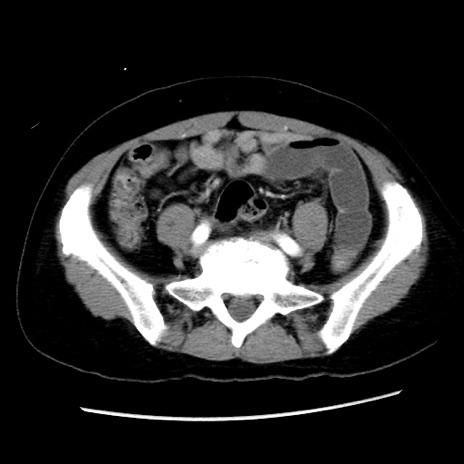

症例10(横断像)

【症例】 50歳代女性

【主訴】 腹痛

【現病歴】前日生レバーを食べた。今朝に排便あり。 昼前に突然発症の腹痛を生じ、当院救急外来を受診した。

【身体所見】 意識清明、腹部:平坦、軟、下腹部やや左を中心に圧痛・反跳痛あり、筋性防御あり

【データ】WBC 7800、CRP 0.07